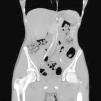

Se realizó una TC abdominal en la que se identificó una pinza aortomesentérica superior de 19° con dilatación y volvulación del duodeno proximal (figs. 1 y 2).